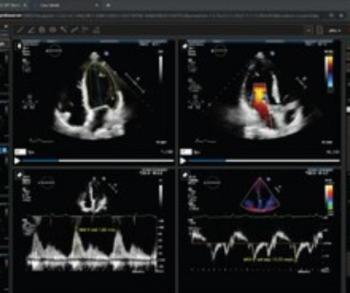

Study Finds AI More Effective Than Sonographer Interpretation of Cardiac Function on Echocardiograms

Based on a review of 3,495 echocardiographic studies to evaluate left ventricular ejection fraction (LVEF), researchers found that cardiologists changed initial artificial intelligence (AI) assessment 16.8 percent of the time and initial sonographer assessment 27.2 percent of the time.